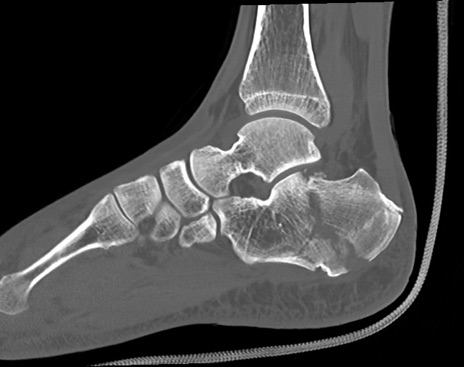

症例37 左足関節CT(矢状断像)

左足関節CT

冠状断像